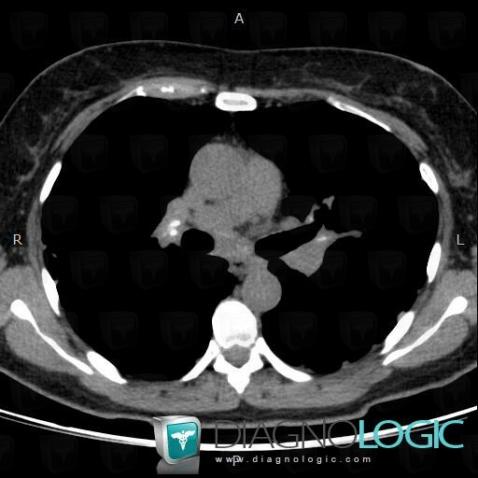

Les images ci-dessous illustrent ce dossier pour les diagnostics Sarcoïdose (lié à Fibrose pulmonaire), Sarcoïdose, pour les modalités (Scanner)

Voici les informations spécifiques à l'image clé ci dessus:

- Diagnostic Sarcoïdose, Localisation(s) Plèvre, comportant les gammes Epaississement pleural